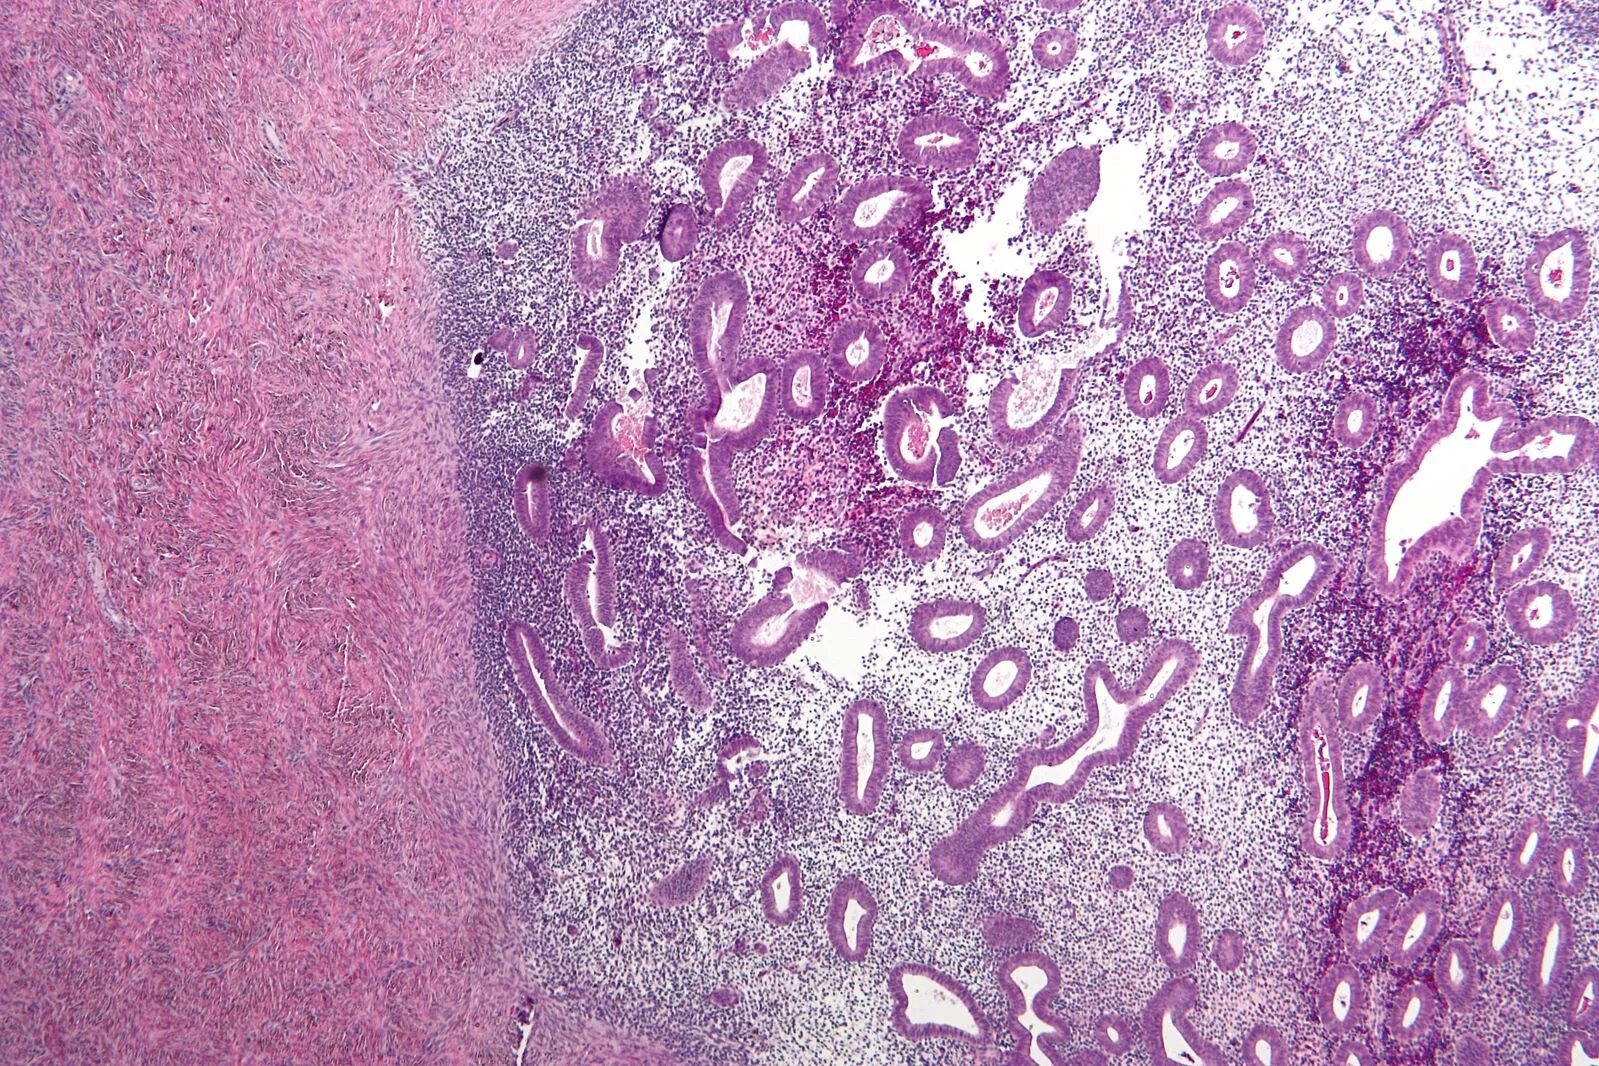

Эндоцервикс клетки метаплазированного эпителия